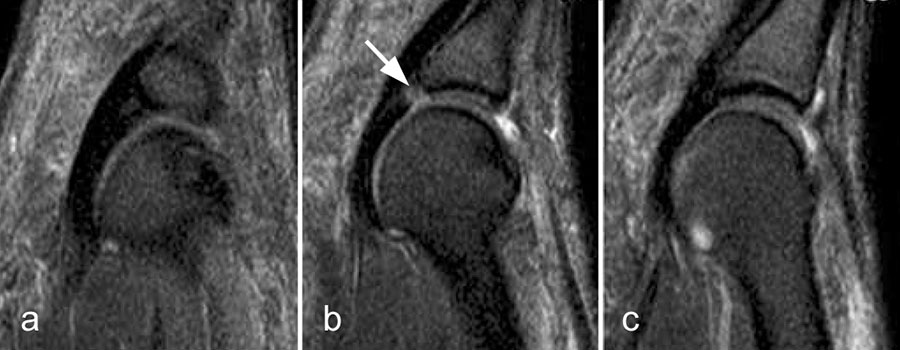

Intermetatarsale Bursitis

Intermetatarsale Bursitis bei rheumatoider Arthritis mit Erguss (a) und deutlicher Synovialitis in mehreren Schleimbeuteln (b).

Zwischen den Metatarsaleköpfchen befinden sich kleine Schleimbeutel, die in der Regel MR-tomographisch nicht zu identifizieren sind. Sie werden erkennbar, wenn sie zarte Flüssigkeitsstreifen enthalten, was noch nicht als pathologisch zu werten ist. Eine signifikante Distension und vor allem eine verstärkte Kontrastmittelanreicherung sind Ausdruck einer Bursitis. Die isolierte Bursitis intermetatarsal ist selten und stets hochverdächtig für das Vorliegen einer rheumatischen Grunderkrankung (Abb. 13).

Häufig sind intermetatarsale Bursitiden als Begleitphänomen bei Rupturen oder Degenerationen der plantaren Platte und auch bei Morton-„Neuromen“.